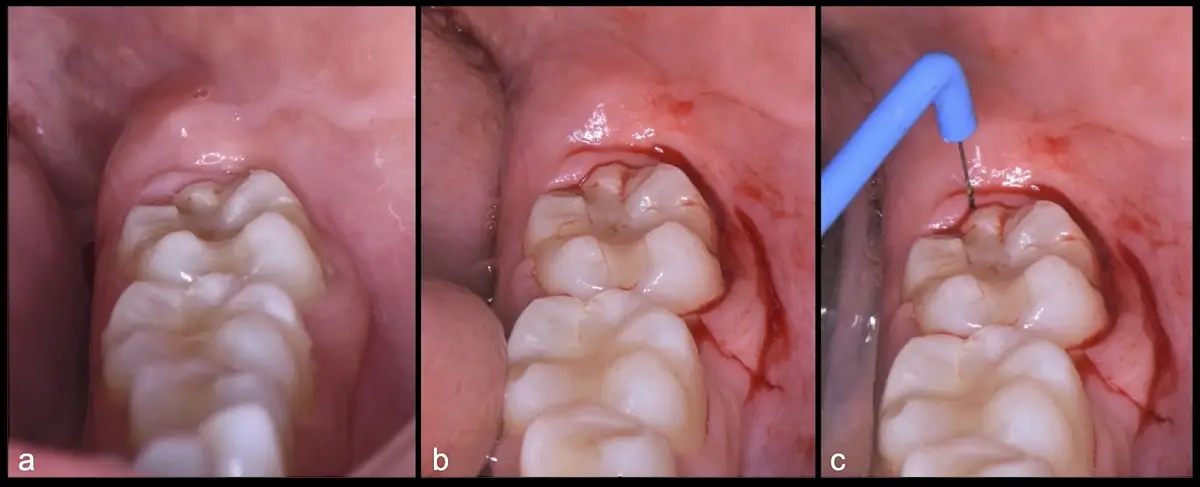

El procedimiento se inicia colocando anestesia troncular para bloqueo del nervio dentario inferior y sus ramas. Luego, se establecerá el diseño de acceso según la disposición de la molar a extraer. Para fines didácticos, se explicará cómo se realizaría la extracción de la molar de la Figura 1: se realiza una incisión horizontal a nivel de la zona retromolar hasta llegar a distal de la segunda molar, continuándose con una incisión intrasurcular hasta mesial de la segunda molar, finalizando con una incisión vertical a espesor total hasta llegar a la línea mucogingival (Figura 2).